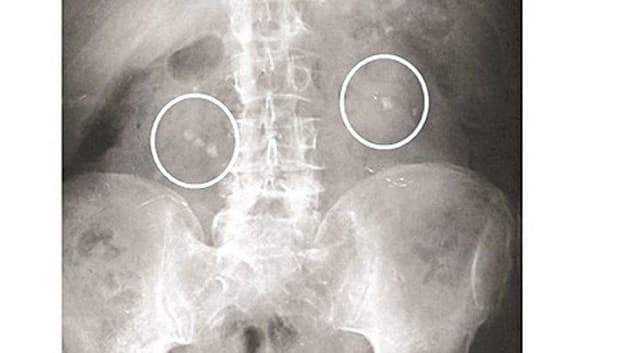

Trước khi thực hiện tán sỏi bác sĩ sẽ thăm khám và chẩn đoán hình ảnh. Các phương pháp thường dùng như: Chụp ảnh X-quang, phân tích nước tiểu, siêu âm,…

– Chẩn đoán phân biệt lâm sàng, xét nghiệm nước tiểu, chẩn đoán hình ảnh, phân tích thành phần cấu tạo sỏi,…